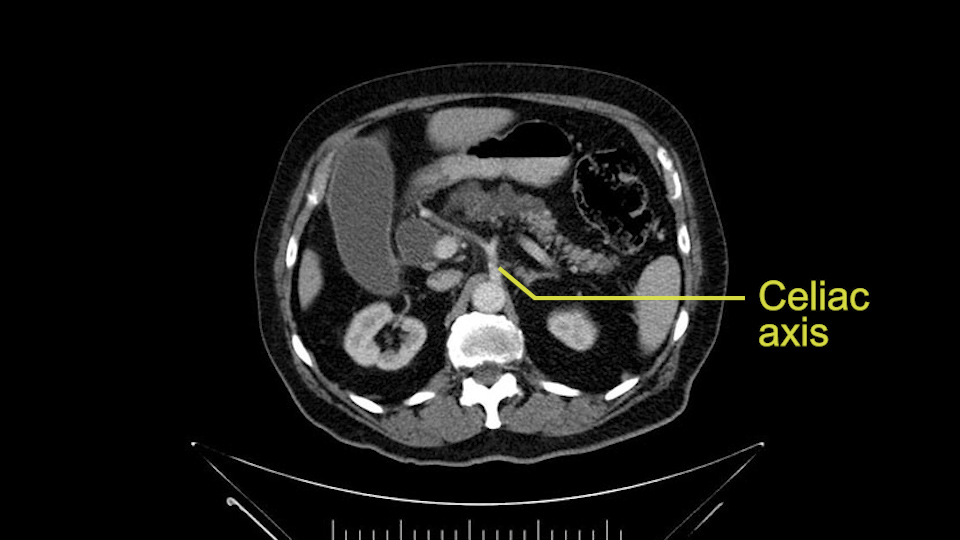

To plan a pancreatoduodenectomy, we start by reviewing the vascular anatomy, especially the origin of the celiac trunk, here, in front of the aorta, looking for any evidence of stenosis. In addition, we look at the origin of the superior mesenteric artery, to look for any branches, and any replaced right hepatic arteries coming from the superior mesenteric artery; which does occur in about 12% of the population.

First, the stenosis of the celiac trunk, which can be caused by arteriosclerosis, especially in a patient who is 83, or in patients who have arcuate ligament; we do see it, sometimes in much younger patients. In those cases, it may be that the circulation of the hepatic artery comes entirely from the gastroduodenal artery and its anastomoses, through the pancreaticoduodenal arteries, coming from the superior mesenteric artery. This means that before the gastroduodenal artery is ligated, we first clamp and wait 30 seconds to a minute, to feel and check the arterial inflow to the liver. If the pulse is diminished or there is a complete absence of the pulse, the surgery should be modified or probably a pancreatoduodenectomy cannot be done, because of the risk - when ligating the gastroduodenal artery - of causing fulminant hepatic ischemia postoperatively.

Para planear una pancreatoduodenectomía, se debe revisar la anatomía vascular, especialmente el origen del tronco celíaco, aquí, por delante de la aorta, buscando areas de estenosis y por otro lado, el origen de la arteria mesentérica superior, para evaluar -sobre todo- si hay ramas, arterias hepáticas derechas provenientes de la mesentérica superior; lo cual ocurre en alrededor del 12% de la población.

La primera que mencionamos, la estenosis del tronco celíaco, que puede ser causada por arterioesclerosis, especialmente en este paciente de 83 años, ó por pacientes que tienen ligamento arcuato; ese sí lo vemos, a veces, en pacientes mucho más jóvenes. En esos casos, puede resultar que la circulación de la arteria hepática provenga completamente a través de la arteria gastroduodenal y sus anastomosis, por las arterias pancreaticoduodenales, provenientes de la mesentérica superior.

Esto quiere decir la precaución que tenemos, es que -antes de ligar la arteria gastroduodenal- durante la pancreatoduodenectomía, hacemos un clampeo, esperamos 30 segundos o un minuto, y palpamos y vemos el pulso hepático. Si el pulso hepático se disminuye o hay ausencia completa del pulso, debe modificarse la cirugía; probablemente no se pueda hacer la Pancreatoduodenectomía, por el riesgo -al ligar la arteria gastroduodenal- de causar una isquemia hepática fulminante en el postoperatorio.